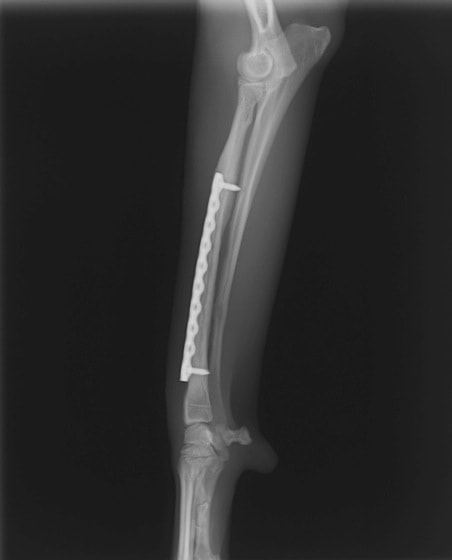

トイプードル 右遠位橈尺骨短斜骨折のALPSによる内固定

Locking Compression Plate

LCPは、スクリュー(ネジ)とプレート(金属の板)をロックする特殊な構造により骨折部位を固定する新しい世代のプレートシステムです。ひとつのホールでロッキングスクリューとスタンダードスクリューの使用を選択できるユニークな構造をしているため、骨折断端間の圧迫を目的とした従来型プレート固定法に加え、高い角度安定性を有するロッキングスクリューを用いた固定法の選択が可能です。従来のプレートシステムでは困難だった部分の骨折や癒合不全の症例に高い治療効果をもたらします。

Advanced Locking plate system と Locking compression plate system

当院ではAdvanced Locking plate system(ALPS)と、Locking compression plate system(LCPS)という骨接合法で骨折症例の治療を行っています。